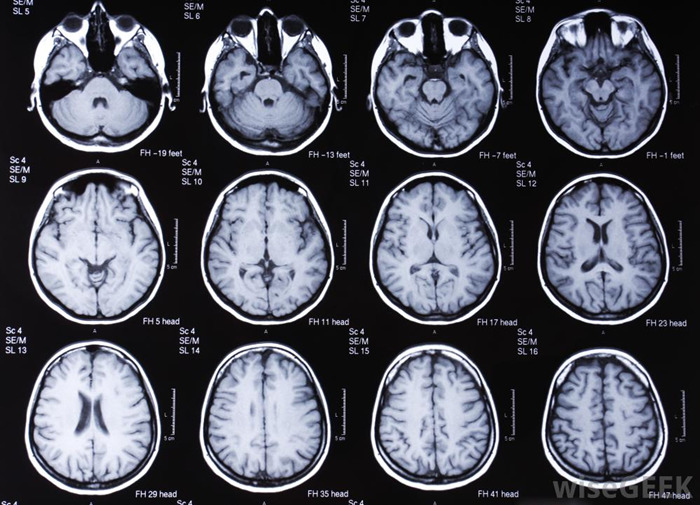

Инструментальная диагностика:

- Топограф, рентген дают оценку структуры головного мозга, а также костей черепа и позвоночника.

- ЭЭГ способствует обнаружению патологически измененных участков мозга.